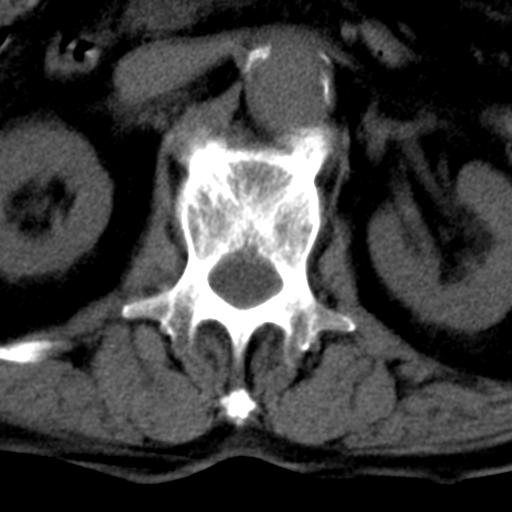

男性 82 主动脉夹层 请大家看看椎体是什么改变啊

腰椎退行性变,明显的骨赘形成,所指低密度灶为正常松质骨。